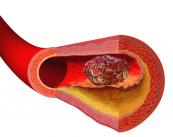

La Trombosis y la Embolia

Diferencia entre la Trombosis y una Embolia